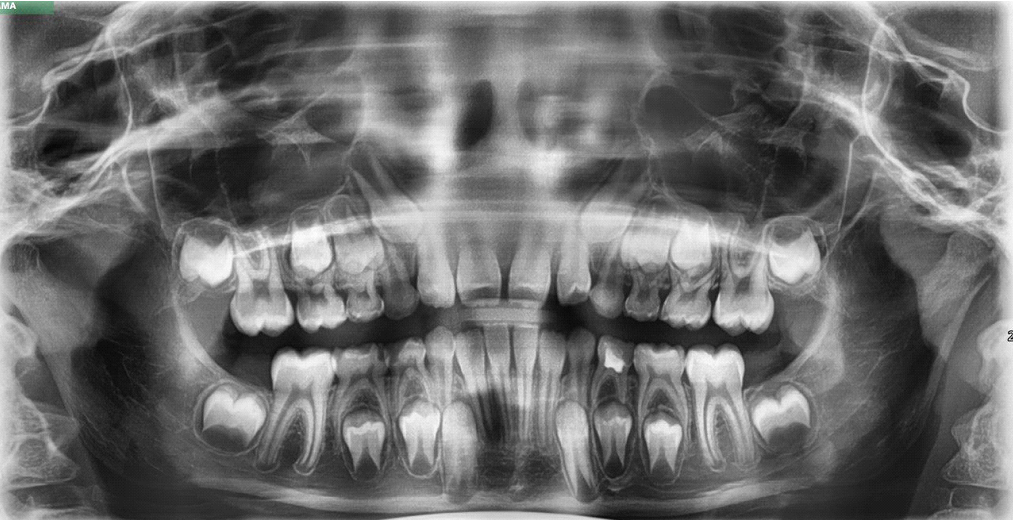

Вот молодой пациент нафарширован зубами (это нормально, часть так называемые молочные):

Временные, постоянные и зачатки постоянных зубов — смешанный прикус.